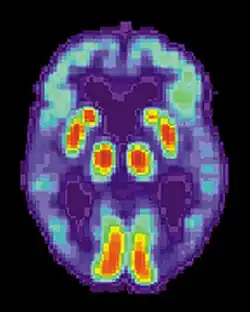

Аппаратура SPECT- и PET-визуализации при её доступности может быть использована для подтверждения диагноза совместно с другими методами оценки, включающими анализ ментального статуса[130]. У людей, уже страдающих от деменции, SPECT, по некоторым данным, позволяет более эффективно дифференцировать болезнь Альцгеймера от других причин, по сравнению со стандартным тестированием и рассмотрением анамнеза[131]. Возможность наблюдать отложения бета-амилоида в мозге живых людей появилась благодаря созданию в Питтсбургском университете Питтсбургского состава B (PiB), связывающегося с амилоидными отложениями при введении в организм. Короткоживущий радиоактивный изотоп углерод-11 в соединении позволяет определять распределение этого вещества в организме и получать картину амилоидных отложений в мозге больного с помощью ПЭТ-сканера[132]. Показано также, что объективным маркером болезни может быть содержание бета-амилоида либо тау-белка в спинномозговой жидкости[133] и крови[134]. Эти два новых метода вызвали предложения о разработке новых диагностических критериев[117][123]. Другие препараты для PET-визуализации: флорбетапир, флутеметамол, флорбетабен, флортауципир.